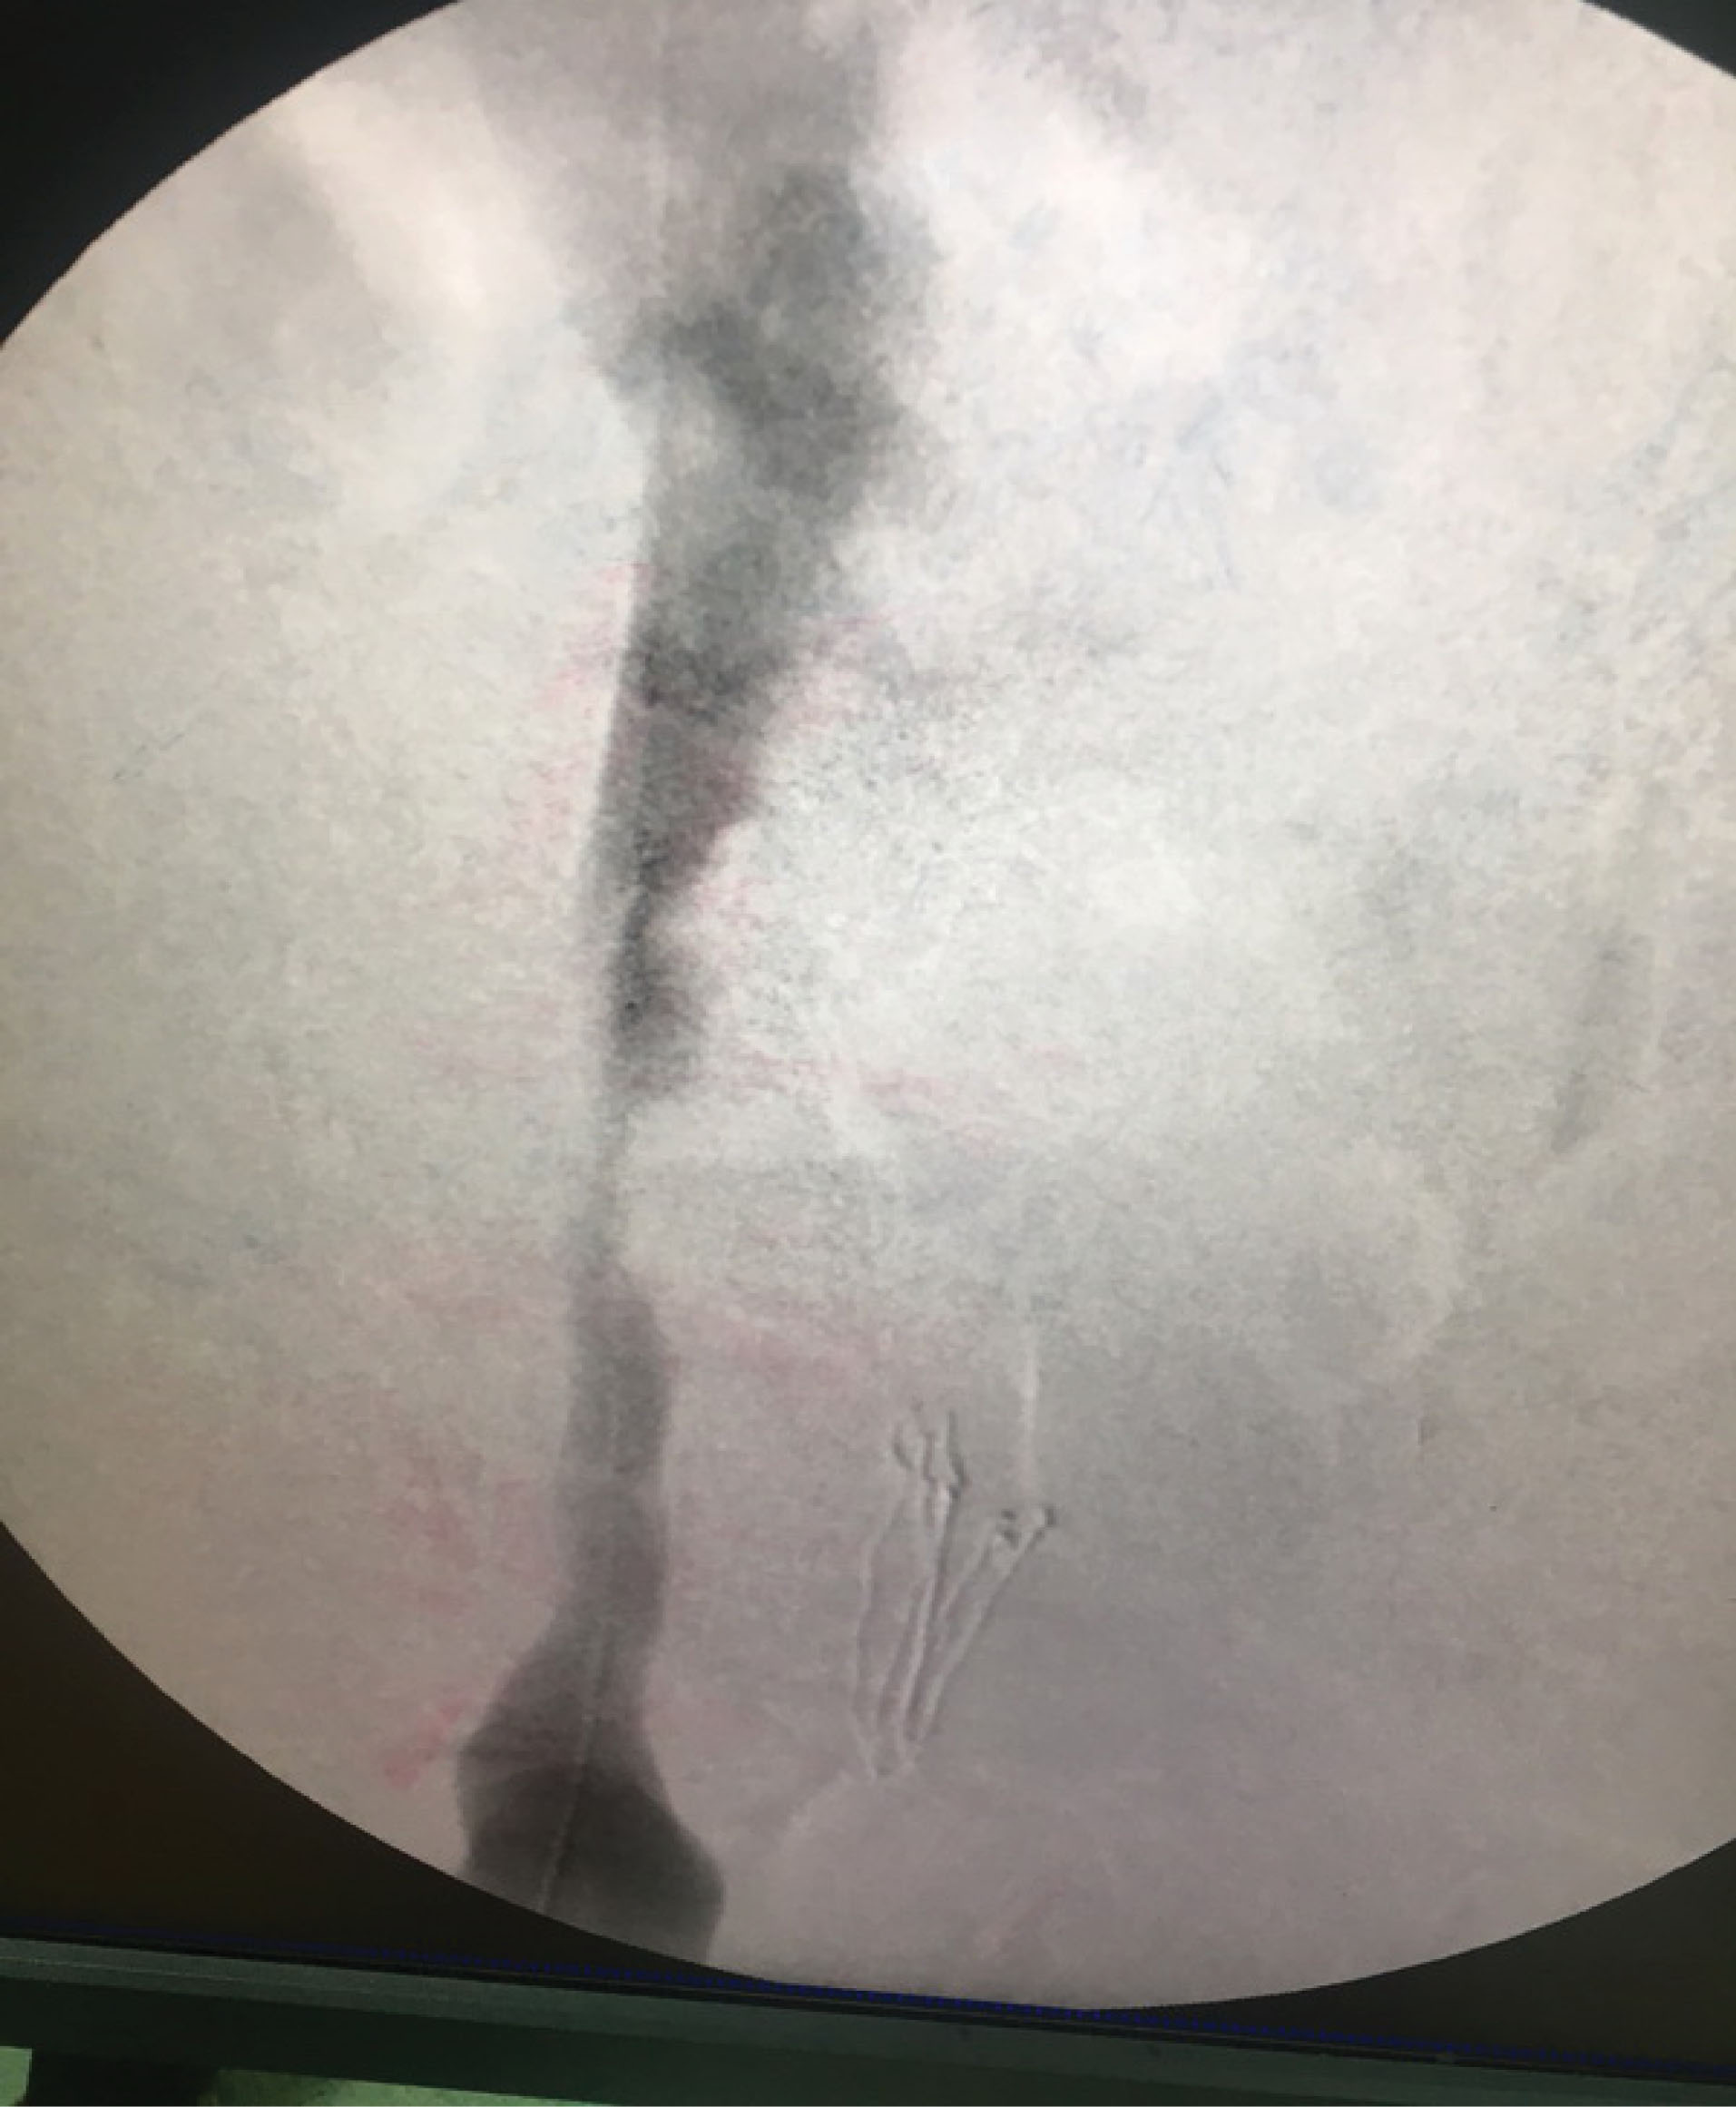

We did venography to reveal the underlying cause of venous stasis in right lower extremity. We did the imaging on prone position. A 5F sheath was introduced through the right popliteal vein. The external iliac vein had severe stenosis and invasion of pelvic mass into the vein was evident. This procedure was done under close monitoring of vital signs and local anesthesia. We transformed the patient to supine position to cannulate right superficial femoral vein (SFV). An 8F sheath was introduced into SFV by ultrasound guidance and Seldinger technique 10cm below the inguinal ligament. The reason for changing the position of the patient was that the procedure of stenting is painful. We wanted to do the procedure under deep sedation and it was not possible to do this in prone position because of general condition of the patient. A repeat venogram was obtained at supine position and similar results were found (). Venography was repeated at 45 and 90 degrees of left lateral oblique views and severe stenosis and tumor invasion were confirmed. A 0.035 hydrophilic standard guidewire was introduced through the sheath and the stenosis was crossed. Then a 40 mm length and 10 mm diameter CONQUEST balloon (BARD) was introduced over the guidewire. Venoplasty of external iliac vein was conducted throughout the stenosis and at proximal and distal parts. Then a venous stent of 80 mm length and 12 mm diameter (VENOVO, BARD) was introduced over the guidewire and deployed in the external iliac vein with the stenosis trapped inside the length of the stent. The completion venogram illustrated dilatation of the stenosis and reestablishment of flow of contrast material through the external iliac vein (). Then a 40 mm length and 12 mm diameter CONQUEST balloon (BARD) was introduced over the guidewire. Balloon dilatation was done through the stent and its proximal and distal landing zones. 7500 units of intravenous heparin was administered during the procedure. A loading dose of 300mg Clopidogrel was administered to the patient after the procedure at the recovery theater. The patient was anticoagulated by heparin for 48 hours and Clopidogrel 75mg daily was also administered during that period. Rivaroxaban 10mg per 12 hours and Clopidogrel 75 mg daily was administered on discharge. The patient was on Aspirin 80 mg daily before the procedure and we advised him to continue the same dose.

jcvtr-13-84-g002

Figure 2. Venoplasty and stenting of right external iliac vein

Dramatic clinical response was evident since postoperative day two. The patient was followed after three and six months. Swelling of right lower extremity was resolved dramatically and the venous ulcer at right medial malleolus was healed. A venous duplex study was done at follow-up visits. Normal venous flow was present.